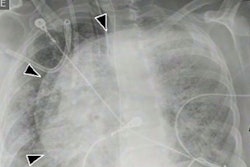

An MR image of a patient in their early 20s shows nerve injury of the left brachial plexus in the neck. The patient experienced left arm weakness and pain after recovering from COVID-19 respiratory illness, which prompted them to see their primary care physician. As a result of the MRI findings, the patient was referred to the COVID-19 neurology clinic for treatment. Image and caption courtesy of Northwestern University.Determining the cause makes treatment more effective, according to the team. If the cause is due to injury from prone positioning, a patient would be referred for rehabilitation or peripheral nerve surgery. If nerve damage has been caused by inflammatory response, the patient should see a neurologist. And if the damage is caused by hematoma, blood thinner medications should be adjusted and surgery may be necessary, according to the group.

Ultrahigh-resolution ultrasound and MR neurography (which visualizes the peripheral nerves) can localize the problem and assess the severity of nerve damage and whether that damage has affected the muscles, according to the team.